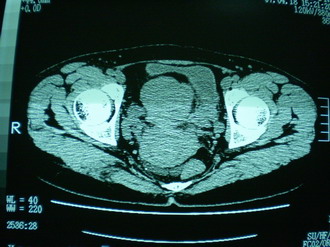

子宫增大,内可见类三角形低密度区,子宫后方可见类圆形团块状影,内部密度不均匀,可见靶样结构,结合病史考虑1子宫后方宫外孕(宫内假孕囊形成)2子宫肌瘤合并妊娠

子宫明显前倾,增大,宫颈增大呈分叶状。子宫直肠窝见不规则形水样低密度。(膀胱胀尿不理想)

考虑:1、宫颈部占位;

2、子宫直肠窝少量积液(盆腔炎所致)。

考虑:1、宫颈部占位(宫颈癌?);

2、子宫直肠窝少量积液。

1、前曲子宫,2、宫颈部占位?3、盆腔及右输卵管积液?宫内积血?4、左侧卵巢囊肿。

宫颈部占位(肌瘤,癌肿);建议强化.